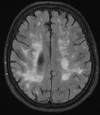

Neurodegenerative diseases are a devastating group of disorders that can be difficult to accurately diagnose. Although these disorders are difficult to manage owing to relatively limited treatment options, an early and correct diagnosis can help with managing symptoms and coping with the later stages of these disease processes. Both anatomic structural imaging and physiologic molecular imaging have evolved to a state in which these neurodegenerative processes can be identified relatively early with high accuracy. To determine the underlying disease, the radiologist should understand the different distributions and pathophysiologic processes involved. High-spatial-resolution MRI allows detection of subtle morphologic changes, as well as potential complications and alternate diagnoses, while molecular imaging allows visualization of altered function or abnormal increased or decreased concentration of disease-specific markers. These methodologies are complementary. Appropriate workup and interpretation of diagnostic studies require an integrated, multimodality, multidisciplinary approach. This article reviews the protocols and findings at MRI and nuclear medicine imaging, including with the use of flurodeoxyglucose, amyloid tracers, and dopaminergic transporter imaging (ioflupane). The pathophysiology of some of the major neurodegenerative processes and their clinical presentations are also reviewed; this information is critical to understand how these imaging modalities work, and it aids in the integration of clinical data to help synthesize a final diagnosis. Radiologists and nuclear medicine physicians aiming to include the evaluation of neurodegenerative diseases in their practice should be aware of and familiar with the multiple imaging modalities available and how using these modalities is essential in the multidisciplinary management of patients with neurodegenerative diseases.©RSNA, 2020.